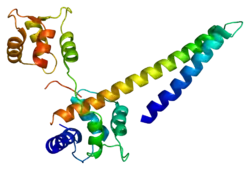

Potassium intermediate/small conductance calcium-activated channel, subfamily N, member 2, also known as KCNN2, is a protein which in humans is encoded by the KCNN2 gene.[3] KCNN2 is an ion channel protein also known as KCa2.2.[4]